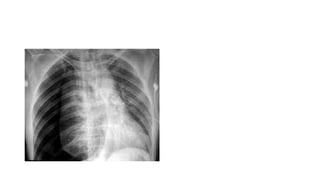

DIAGNOSIS

• eFAST

• fuid in the pericardial sac

• Most reliable

• chest radiography

• looking for an enlarged heart shadow